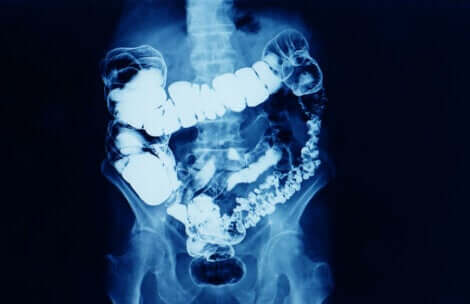

Il glicerolo è il principio attivo delle supposte di glicerina ed è una sostanza che esercita un’azione lassativa se somministrata per via rettale. Questo effetto si ottiene perché la supposta ammorbidisce le feci e produce un lieve effetto irritante locale stimolando la peristalsi intestinale.

- Effetto irritante locale sulla mucosa rettale (l’effetto irritante non influisce sulle pareti intestinali): il retto si contrae favorendo l’espulsione delle feci.

- Effetto osmotico: il glicerolo assorbe l’acqua che, inseme all’effetto lubrificante, ammorbidisce le feci e ne facilita l’espulsione.

L’azione avviene dai 15 minuti a un’ora dopo l’applicazione. Il glicerolo non viene assorbito ed è quasi interamente eliminato attraverso le feci.

Si parla di stitichezza quando la frequenza delle evacuazioni diminuisce. È il sintomo di un rallentamento del transito intestinale.